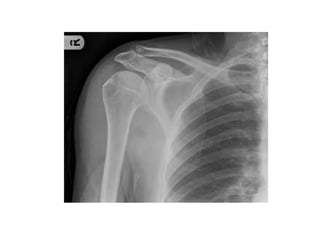

SHOULDER

GIRDLE

ACROMION PROCESS

• It is an anterolateral projection of spine

• Arches over the glenohumeral ( shoulder ) joint

• Articulates, via a small oval facet with clavicle

GLENOID CAVITY

• Lateral angle of scapula is marked by a shallow,

comma-shaped glenoid cavity

• It articulates with head of humerus to form

glenohumeral joint

CORACOID PROCESS

• A hook-like structure that projects anterolaterally

• Positioned directly inferior to lateral part of

clavicle

• Small distinct suprascapular notch lies

immediately medial to root of coracoid process

ARTICULATIONS OF SCAPULA

• Glenoid cavity - Humerus

• Acromion – Clavicle